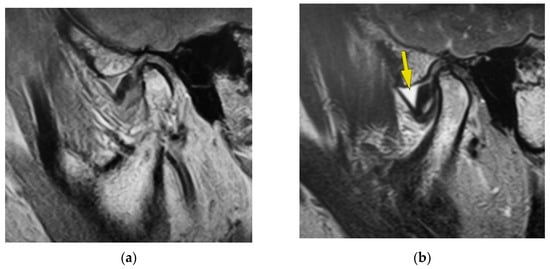

Figure 1 indicates the MR image of one patient in this study with recognized disc displacement without reduction. This MR image is of the left temporomandibular joint of a 48-year-old woman with left temporomandibular joint pain. Proton density-weighted sagittal oblique cross-section imaging in the closed mouth position shows disc displacement (Figure 1a). The articular disc is recognized at the anterior position of the mandibular condyle, and disc deformation was also observed. Bone deformation was not recognized in this image. The T2-weighted sagittal oblique cross-section imaging in the closed mouth position shows temporomandibular joint effusion, as shown by the yellow arrow (Figure 1b). The part observed as the hyperintense area is joint effusion, observed at the superior articular cavity. The amount of synovial fluid in the joint effusion was observed as fluid with plenitude. Proton density-weighted sagittal oblique cross-section imaging at the maximum mouth-opening position shows the articular disc at the anterior position of the mandibular condyle, namely, disc displacement without reduction (Figure 1c). T2-weighted sagittal oblique cross-section imaging at the maximum mouth-opening position shows temporomandibular joint effusion, as shown by the yellow arrow (Figure 1d). The part of the hyperintense area is joint effusion, as observed at the superior articular cavity. The amount of synovial fluid on joint effusion was recognized as fluid with plenitude.

Figure 1.

MR image of one patient with disc displacement without reduction. (a) Proton density-weighted sagittal oblique cross-section imaging at the closed mouth position. (b) T2-weighted sagittal oblique cross-section imaging at the closed mouth position. The yellow arrow indicates the area of joint effusion. (c) Proton density-weighted sagittal oblique cross-section imaging in the maximum mouth-opening position. (d) T2-weighted sagittal oblique cross-section imaging in the maximum mouth-opening position. The yellow arrow indicates the area of joint effusion.